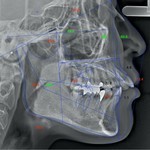

4⃣ 精密検査 について

③各種レントゲン

精密検査で取らせていただいた資料をもとに、矯正担当歯科医師とインビザライン社のAIおよび担当技術者の協働で治療計画を練り上げていきます。このステップは、矯正治療の質(期間や仕上がり)を大きく左右する最重要ステップと言えます。クリンチェックソフトウェアというインビザライン独自のソフトで行っております。計画説明時には、歯並びの変化予測(3D)をモニター上でお見せいたします。また、必要な方には横顔の変化予測もお見せすることが可能です。詳細に関しましては下リンク先、当院のインビザライン特設ページにて解説しております。歯並びの変化がわかる動画なども用意しております。ぜひご覧ください。